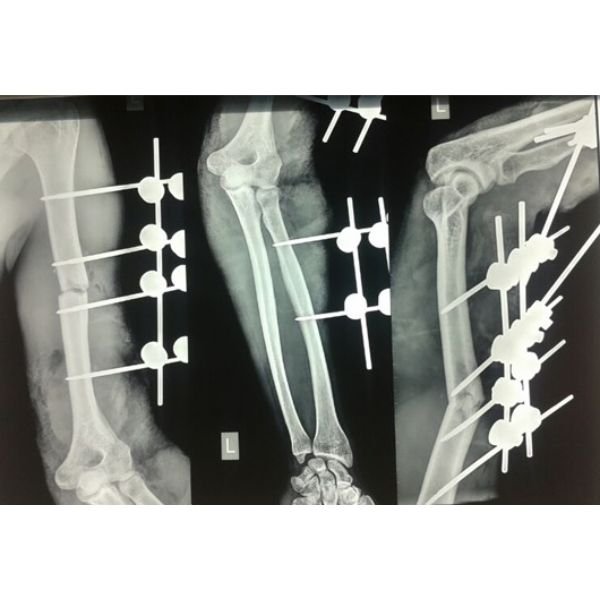

Open Elbow Fracture

Complex Leg Injury